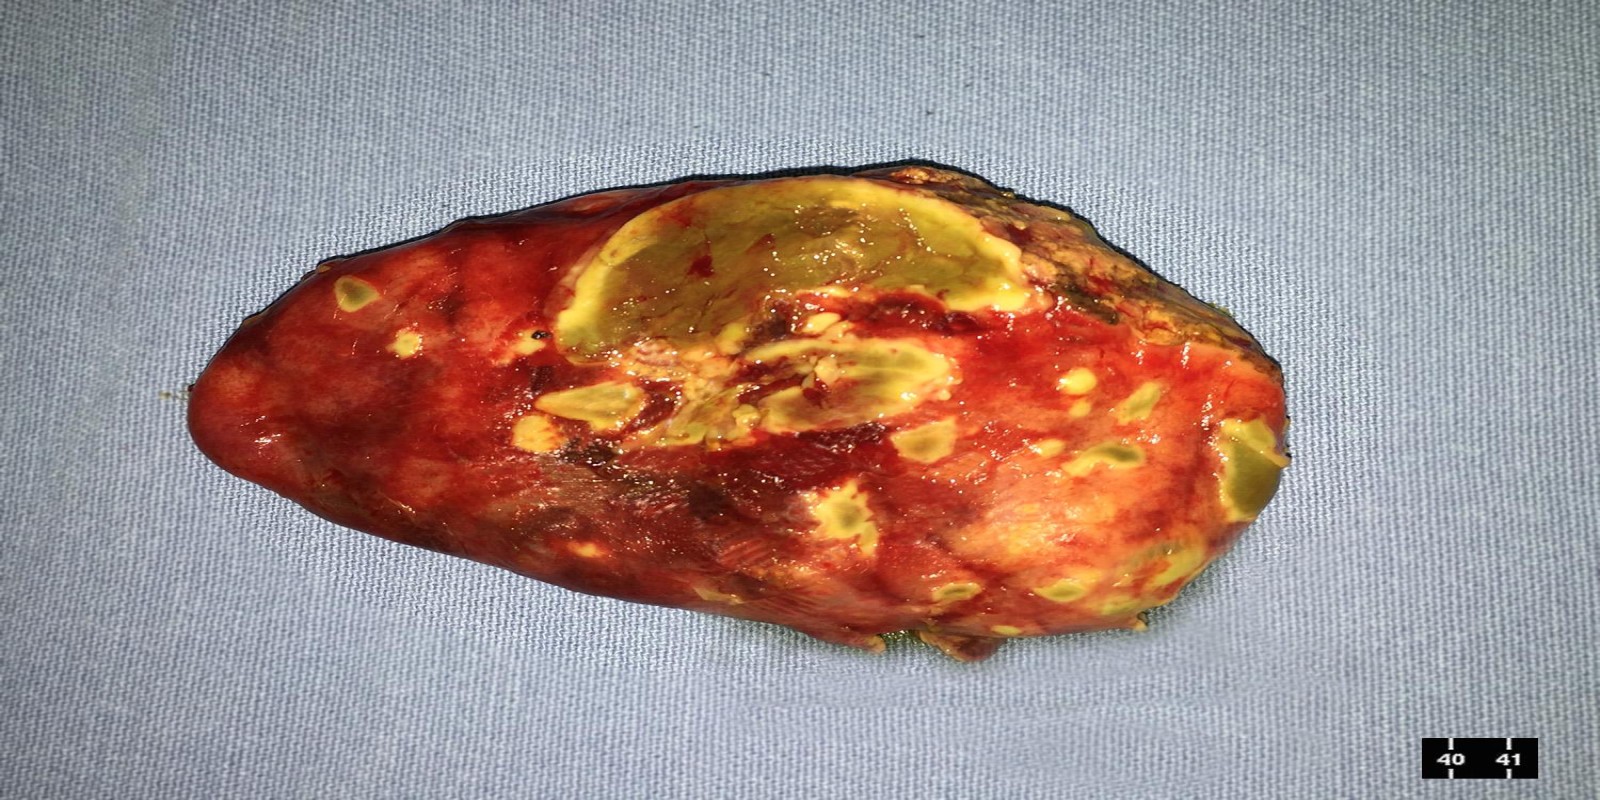

Caso Código 125A de Colecistite Aguda

Cod.: 125A